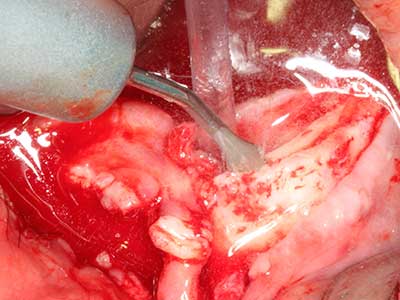

Abb. 18: Präparation eines Kortikalis-Deckels mit der Piezo-Knochensäge (Piezomed, W&H).

Abb. 19: Operationssitus nach Neurolyse und Osteomentfernung.